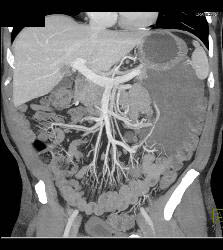

Antral Carcinoma With Celiac Nodes